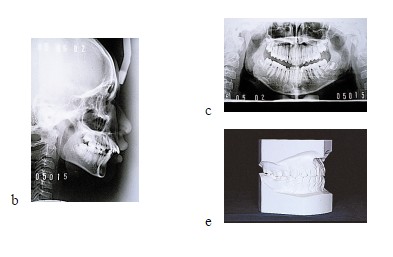

※齒顎矯正主要分類